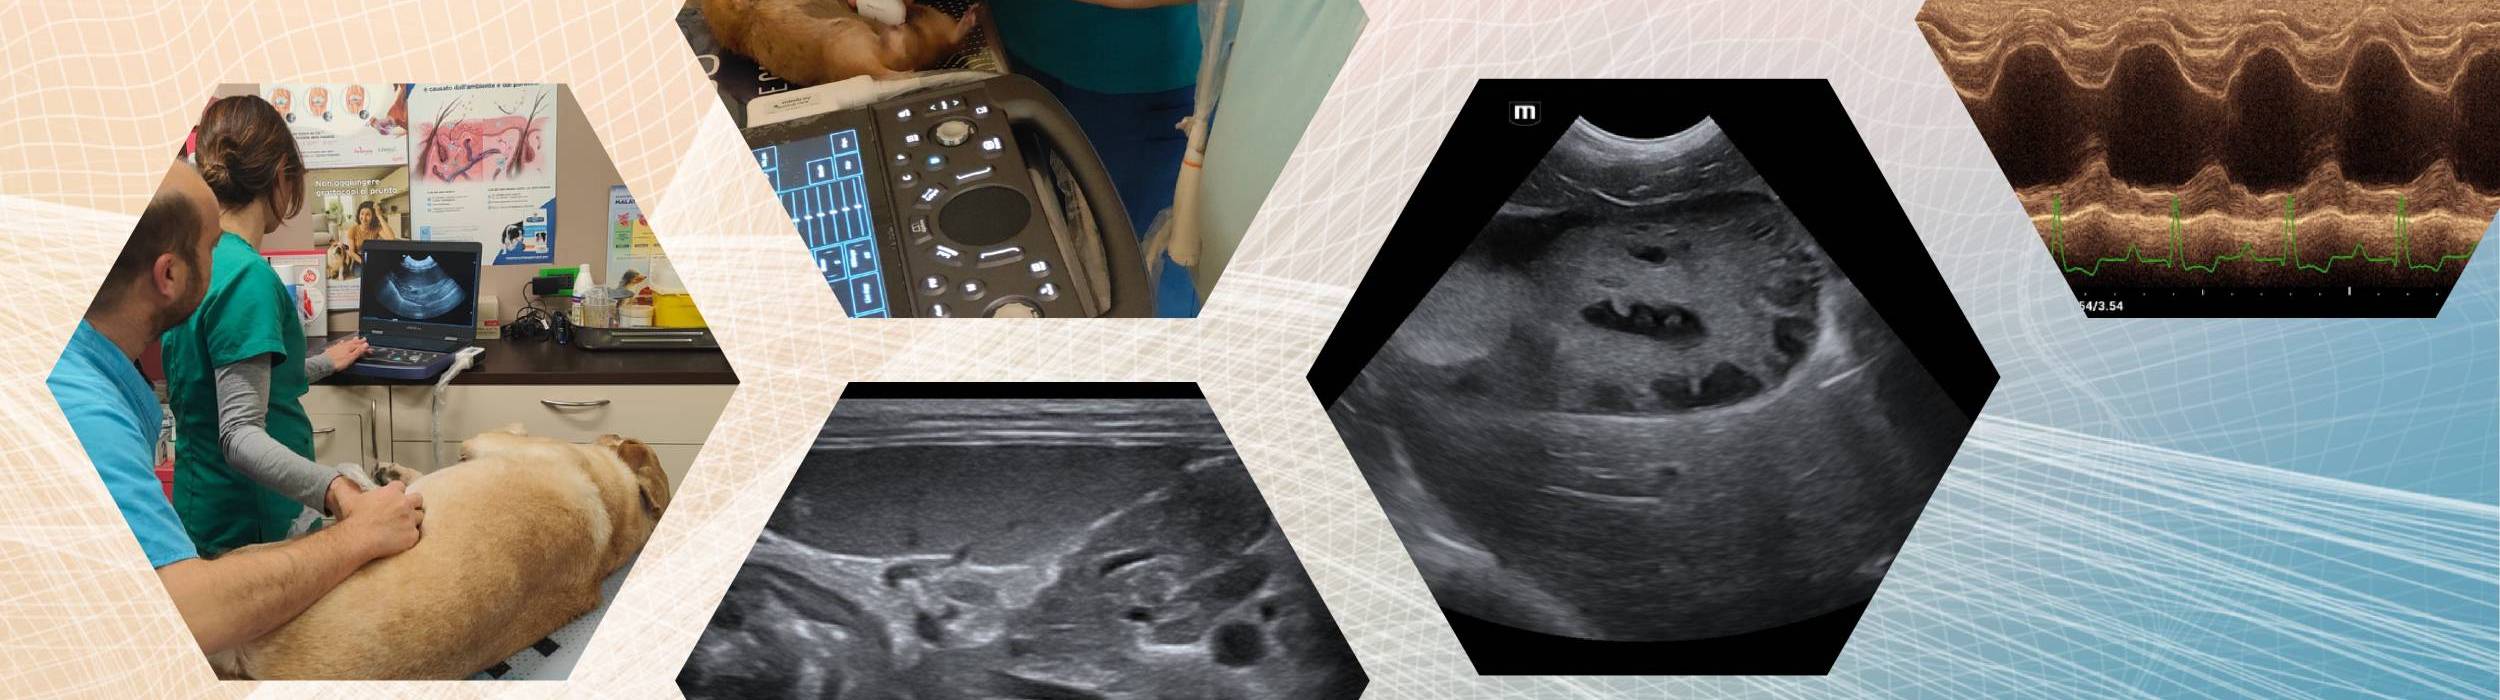

Il corso base di ecografia addominale veterinaria è dedicato a veterinari che desiderano acquisire solide basi teoriche e pratiche nell’esecuzione dell’esame ecografico addominale nel cane e nel gatto.

L’obiettivo è fornire un protocollo di scansione sistematico e riproducibile, sviluppando:

Il percorso alterna teoria e pratica con impostazione progressiva e altamente applicativa.

Parte teorica

• Fisica degli ultrasuoni applicata alla clinica

• Strumentazione ecografica e ottimizzazione dei parametri

• Tecniche di scansione

• Esame addominale sistematico step-by-step

• Approccio diagnostico ai principali organi addominali

Parte pratica

• Sessioni in piccoli gruppi con supervisione di tutor qualificati.